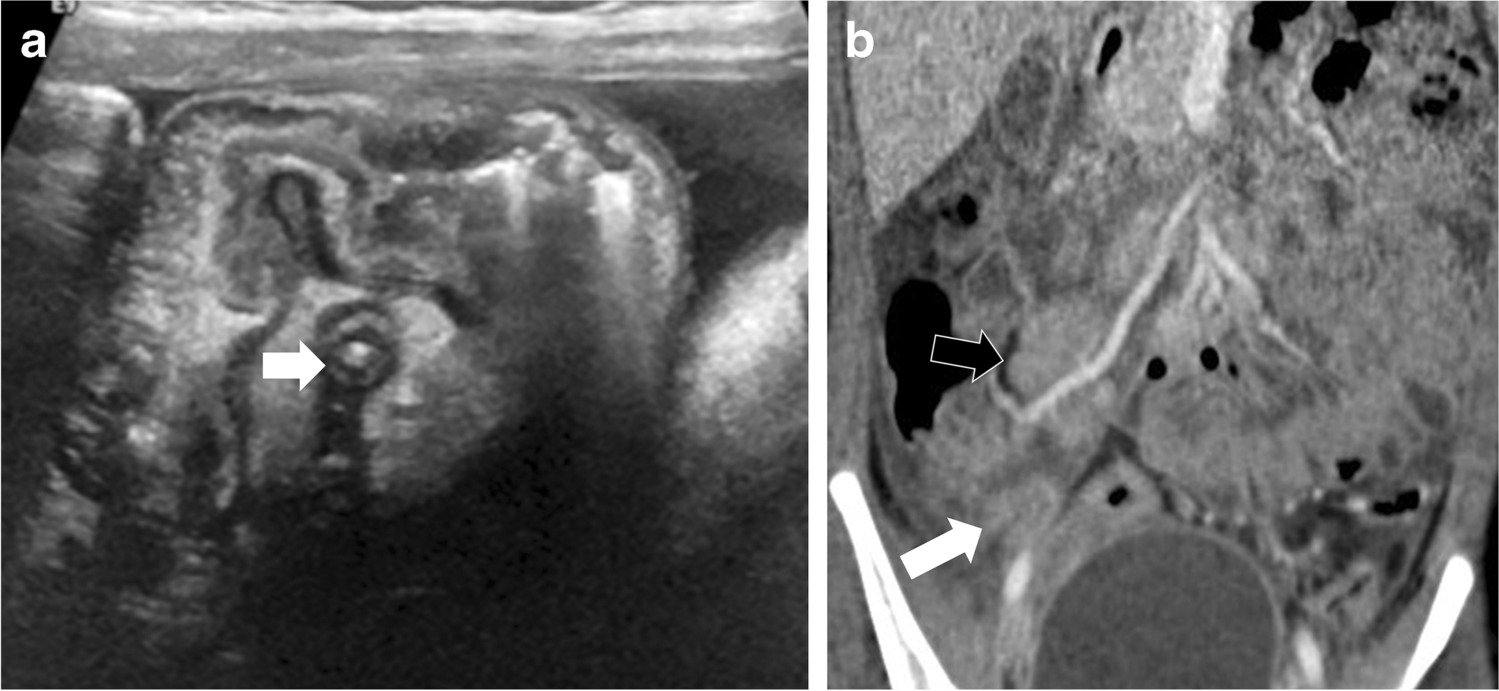

Fig. 2

Case 4: An 8-year-old girl presented with abdominal pain, fever, and vomiting. a Initial transverse US section of right iliac fossa on presentation shows inflamed appendix (arrow) with inflammatory changes. Findings were suspicious for appendicitis. b CT scan (coronal post-contrast) shows multiple enlarged ileocolic lymph nodes (black arrow), largest 20 mm in short axis, free fluid in right iliac fossa, inflamed mesentery, ileal and cecal thickening and inflamed appendix (8 mm, white arrow)

The most common imaging finding in our study was the presence of free fluid, mesenteric inflammation and mesenteric lymphadenopathy (Figs. 1, 2, 3 and 4). We noted that the abnormal nodes were quite prominent, with an average short-axis size of 11.9 mm and average long-axis size of 19.1 mm. Half the children with lymphadenopathy (6/12) had more than six enlarged mesenteric lymph nodes. It is possible that the particularly prominent size of nodes is a phenomenon of PIMS-TS, noting that multiple large lymph nodes are not generally seen in acute appendicitis. Such enlarged lymph nodes can be seen in inflammatory bowel disease (IBD), which generally has small bowel wall asymmetrical thickening (along the mesenteric border), segmental mural enhancement and mesenteric fat expansion [27, 28]; however, the advanced cases of IBD are usually associated with small-bowel stricture, ulcerations and sacculation, fistulas and abscess formation [29].

Another important observation in our study is evidence of appendiceal involvement in 7/23 (30%) cases, which is contrary to the current literature on PIMS-TS (Figs. 1, 2, 3 and 4). In a routine clinical setting, acute appendicitis (enlarged appendix ≥6 mm) is commonly associated with peri-appendiceal fat-stranding, focal cecal apical thickening (arrowhead sign), adenopathy, fluid in right paracolic gutter or appendicolith [27]. In our study, all cases with appendiceal thickening also had distal ileum (not limited to ileo-cecal junction) and cecum (circumferential wall thickening extending to involve the ascending colon in some cases) involvement, in addition to mesenteric inflammation, lymphadenopathy, and free fluid (Fig. 4).